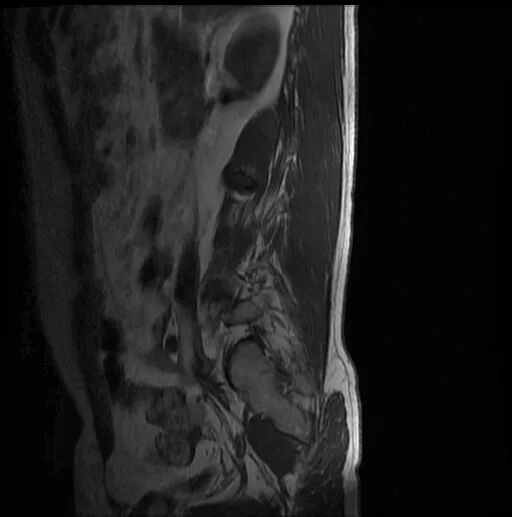

術(shù)前影像資料

圖4:術(shù)前MRI

?